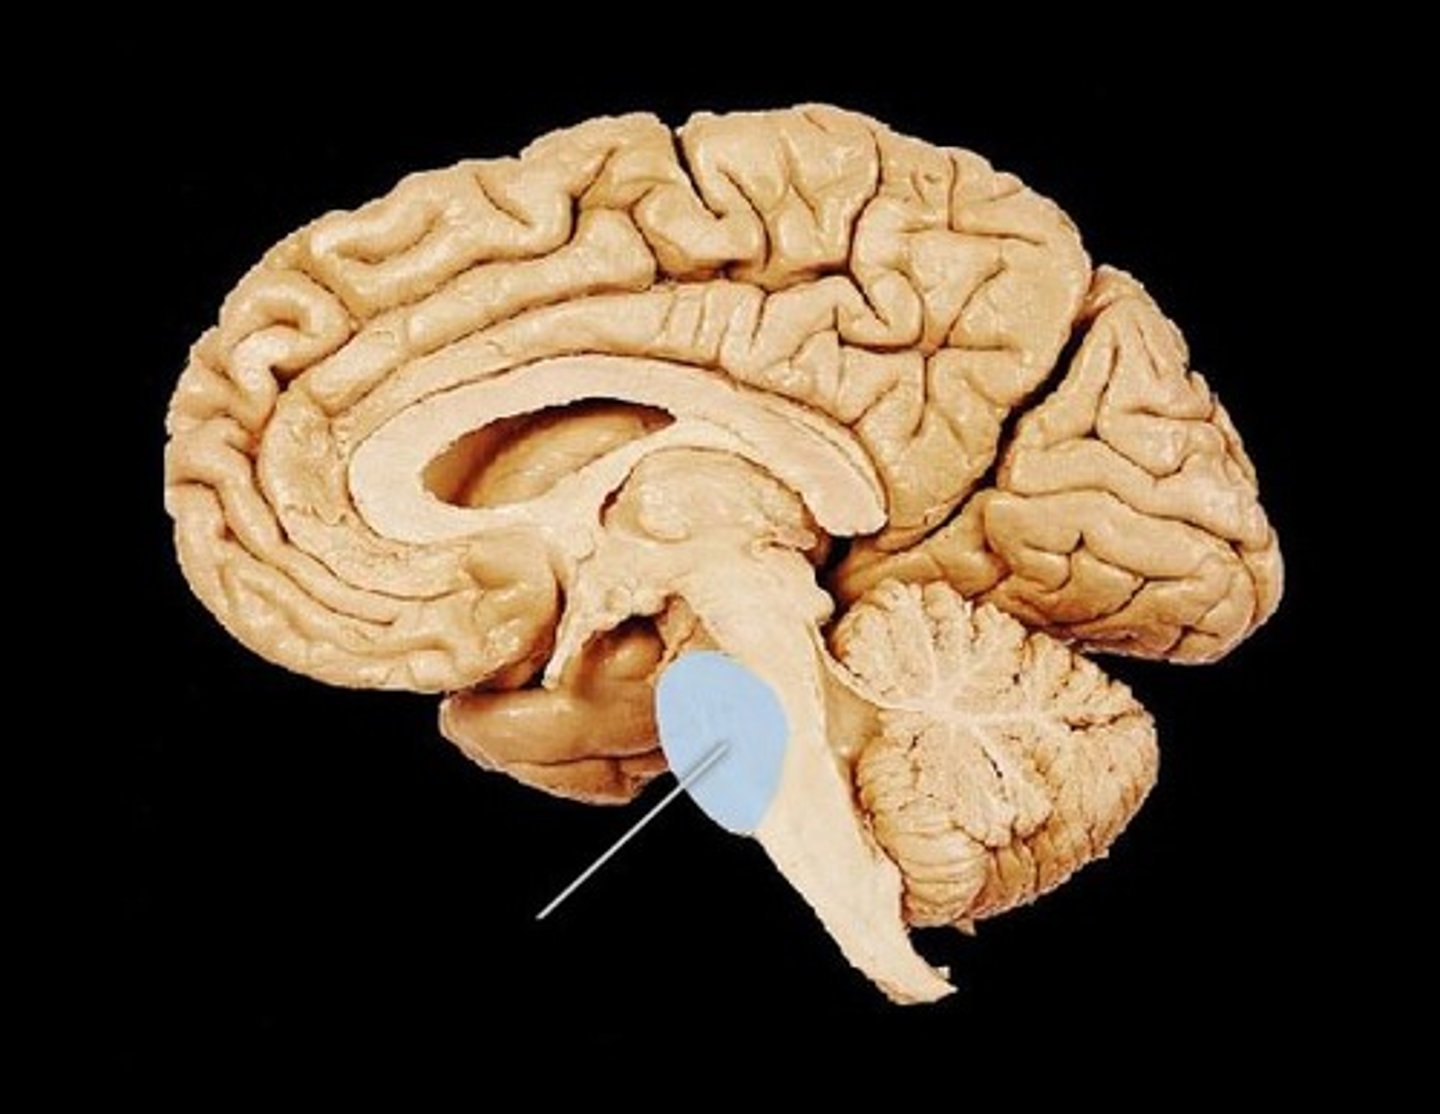

diencephalon

thalamus and hypothalamus

thalamus

relay station for all somatosensory information

intermediate mass

connection between the two thalami across the third ventricle, dumbbell shape

hypothalamus

brain region (many nuclei) in charge of maintaining homeostasis

pituitary gland

produces hormones

mammillary bodies

olfactory relay stations

epithalamus

region above midbrain that contains pineal gland

pineal gland

regulates sleep-wake cycles, secretes melatonin

cerebellum

balance, equilibrium, gross motor movement

cerebrum

cerebral cortex

outer region of the cerebrum, containing sheets of nerve cells; gray matter of the brain

corpus callosum

the large band of neural fibers connecting the two brain hemispheres and carrying messages between them

septum pellucidum

membrane that separates lateral ventricles

basal nuclei

internal masses of gray matter, smooth out motor movement

fornix

band under septum pellucidum